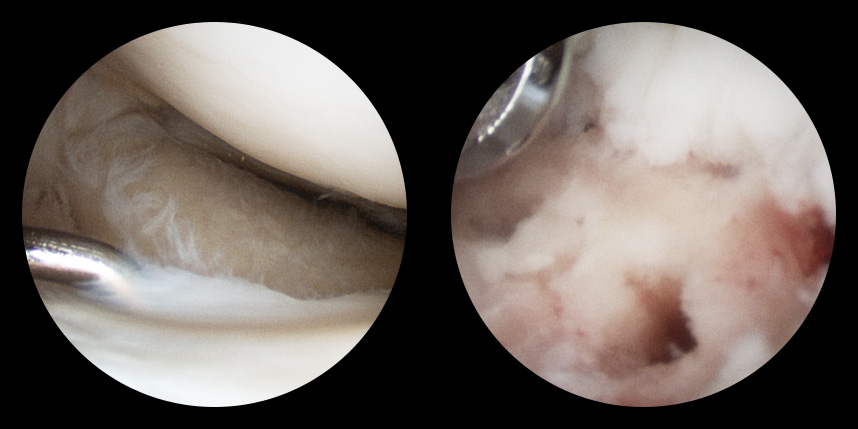

연골손상의 단계를 결정할 때 사용하는 ICRS 단계에서 3단계 미만의 연골손상에 사용하는 방법으로 울퉁불퉁한 표면을 다듬어 주는 정도의 수술법입니다.

4단계 이상일 경우 미세천공술을 기본으로 시행하며, 미세천공술로 나온 본인의 골수줄기세포와 함께

연골 생성을 촉진할 수 있는 “재료”를 같이 주입하는 치료를 시행합니다.

손상된 연골 부위에 작은 구멍을 뚫어 골수에서 나오는 줄기세포를 이용하여 연골 재생을 유도하는 방법으로 근본적으로 섬유연골(정상연골보다는 약한 연골)로 재생된다고 알려져 있습니다.

특수하게 농축하여 제작된 6% 콜라겐(리젠실603) 또는 9% 콜라겐(이엔카티)을 천공술을 시행한 부위에 덮어 주어 미세천공술 단독보다 좋은 치료 결과를 기대할 수 있습니다.

본원에서는 미세천공술, 콜라겐주입술, 카티스템 치료를 주로 하고 있습니다.